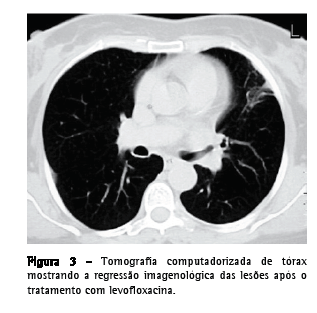

Uma paciente do sexo feminino, 55 anos de idade, caucasiana, não fumante, secretária, procurou atendimento no serviço de emergência. Tinha história de hepatite B crônica, hipertensão arterial, dislipidemia mista e múltiplas cáries dentárias não tratadas. Relatou que há três semanas havia iniciado quadro de dejeções diarréicas diárias, azia, desconforto retroesternal agravado pelo decúbito dorsal, astenia, anorexia e emagrecimento (5 kg). Uma semana depois haviam surgido toracalgia esquerda de características pleuríticas com agravamento progressivo, acessos freqüentes de tosse seca ao esforço e pico febril isolado. O eletrocardiograma foi normal, e a endoscopia digestiva alta revelou um cárdia complacente e gastrite antral. A telerradiografia de tórax mostrou hipotransparência heterogênea, esboçando perda de substância em seu seio, no terço médio do campo pulmonar esquerdo. A tomografia computadorizada de tórax evidenciou a presença de uma massa de 4 cm com conteúdo heterogêneo e continuidade pleural ao nível da língula e a presença de dois micronódulos subpleurais na região posterior do campo pulmonar direito (Figura 1). Procedeu-se ao estudo etiológico considerando-se a hipótese diagnóstica de neoplasia pulmonar como a mais provável. Do estudo analítico, salientam-se os seguintes resultados: velocidade de hemossedimentação = 98 mm/1a h; antígeno do câncer 125 = 63,3 U.mL-1 (<35,0); antígeno carcinoembriogênico = 3,55 ng.mL-1 (<2,5) e discreta elevação da proteína C reativa. O estudo imunológico sérico, os marcadores virais e o estudo analítico final não revelaram outras alterações relevantes. Os resultados da colonoscopia, da ultrassonografia abdominopélvica, da mamografia e da citologia cérvico-vaginal foram normais. A primeira fibrobroncoscopia realizada mostrou sinais inflamatórios difusos ao nível da língula. Os resultados do exame citológico de aspirado, lavado brônquico e lavado broncoalveolar foram negativos para células neoplásicas. O exame microbiológico em aerobiose foi também negativo, assim como a pesquisa de bacilos álcool-ácido resistentes. A paciente foi então submetida à biópsia aspirativa transtorácica (BAT), que, ao exame citológico extemporâneo, mostrou um processo inflamatório com supuração. Face a este resultado provisório, iniciou-se a antibioticoterapia com levofloxacina 500 mg via oral ao dia, e decidiu-se realizar uma segunda fibrobroncoscopia. Entretanto, o exame citológico da BAT revelou aspectos morfológicos compatíveis com a presença de Actinomyces, confirmada pelo exame microbiológico cultural do lavado brônquico e broncoalveolar da segunda fibrobroncoscopia, no qual se identificou A. naeslundii (Figura 2). A pesquisa de bacilos álcool-ácido resistentes foi negativa. Dada a melhoria clínica e radiológica após um mês de tratamento (Figura 3), optou-se por manter a antibioticoterapia já iniciada, cuja posologia foi alterada: levofloxacina 500 mg endovenoso ao dia por quatro semanas e, depois, 500 mg po qd. Não se verificou iatrogenia à terapêutica, a qual foi mantida por 16 semanas, até a completa normalização radiológica. Analiticamente constatou-se uma redução da velocidade de hemossedimentação e uma redução de ambos os marcadores tumorais inicialmente alterados, assim como a normalização da proteína C reativa. A paciente foi também submetida a tratamento dentário.